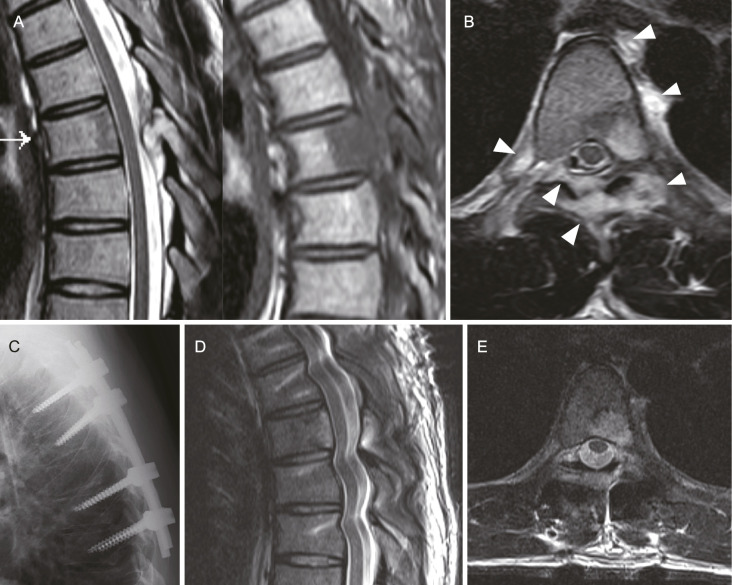

Results: Four male patients aged between 21 and 28, each with a single spinal LCH lesion (T6, T5, and C5) except one case (T5 and T7), were treated. Diagnoses were confirmed via biopsy (two open, two needle biopsies). Whole-body computed tomography or bone scintigraphy revealed no additional LCH lesions in any patient, except in one patient with a small lung nodule. All patients presented with severe back or neck pain and pathological fractures at the affected vertebra. Thoracic LCH cases received percutaneous pedicle screw fixation, while the cervical case was managed with conventional posterior instrumentation using lateral mass screws. After surgery, all patients experienced significant pain relief, halted bone lysis, and rapid new bone formation. One patient underwent chemotherapy postsurgery. Over 3 years of follow-up, imaging studies revealed no recurrences of the disease.

Conclusions: Posterior instrumentation, without the need for curettage or bone grafting, is a promising surgical treatment for adult spinal LCH. This method may effectively halt lesion progression, prevent spinal deformity, and avert neurological deficits in the patients with progressive spine lesion where conservative treatment may not adequately prevent vertebral fractures.